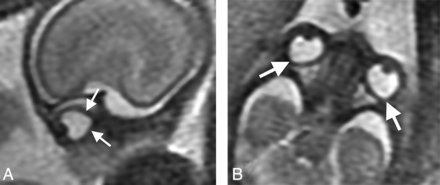

All globes were generally symmetric to one another in shape bilaterally. Nonelliptic globe morphology (focal convexity of the posterolateral margins) was universal until 22 weeks' gestation in both the axial and sagittal planes (Figs 3 and 4A, -B). Thereafter, globe morphology gradually changed. At 22–24 weeks, most patients had nonelliptic globes (sagittal and axial planes), and a few were transitional, approaching an elliptic shape (abnormal only on axial images). At 25–28 weeks, noticeably milder changes occurred, with minor nonelliptic globe morphology generally only visible in the axial plane in most patients. At 29 weeks and beyond, almost all patients demonstrated elliptic globe morphology with no more than minimal contour deformity noted (Fig 4 and Table). All patients with follow-up fetal MR imaging examinations (n = 25) had progression of globe morphology toward an elliptic shape in accordance with this timeline.

Sagittal (A) and axial (B) “fetography” T2WI (TR/TE, 5000/163 ms) of a normal fetal brain at 20 weeks' gestational age. The globe morphology is conical, with angulation of its posterior (arrows, A) and posterolateral (arrows, B) margins.

Sagittal (A) and axial (B) T2 HASTE (TR/TE, 1270/80 ms) of a normal fetal brain at 18 weeks' gestational age. The globe morphology is conical with angulation of its posterior (arrows, A) and posterolateral (arrows, B) margins. Follow-up sagittal (C) and axial (D) T2 HASTE (TR/TE, 1270/81 ms) of a normal fetal brain from imaging performed on the same patient at 30 weeks' gestational age. Ocular globe morphology is round/elliptic in the axial and sagittal planes. Fetal vasculature is not visible.